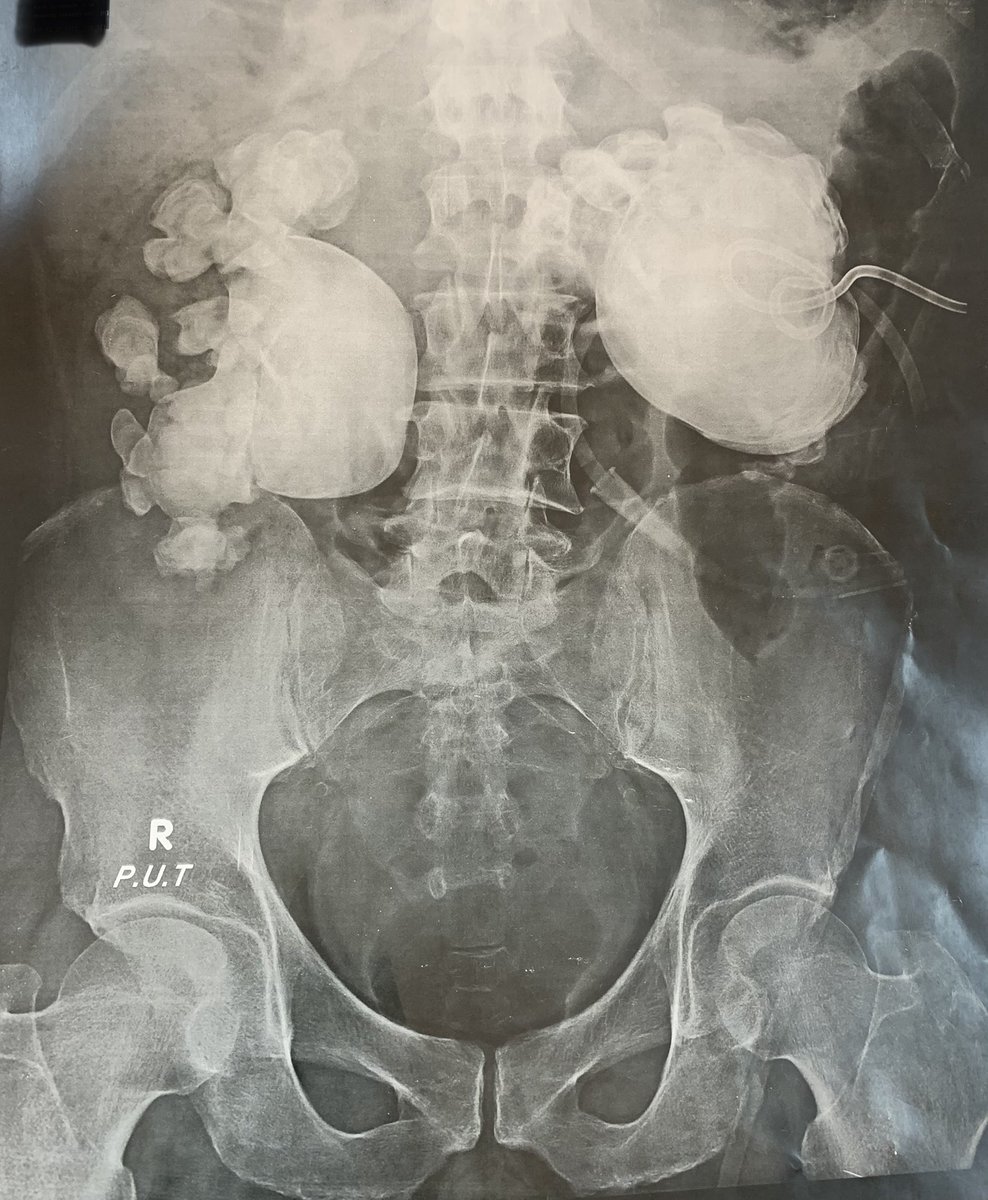

Pt cleared

Rt open pyelonephrolithotomy & Lt nephrectomy for NFK.

Small residual Rt lower calyceal stone.

Mohamed Elsaqa@elsaqa2020

It is not IVU nor antegrade contrast study !! It is a Plain KUB 😳 in a pt presented with loin pain.